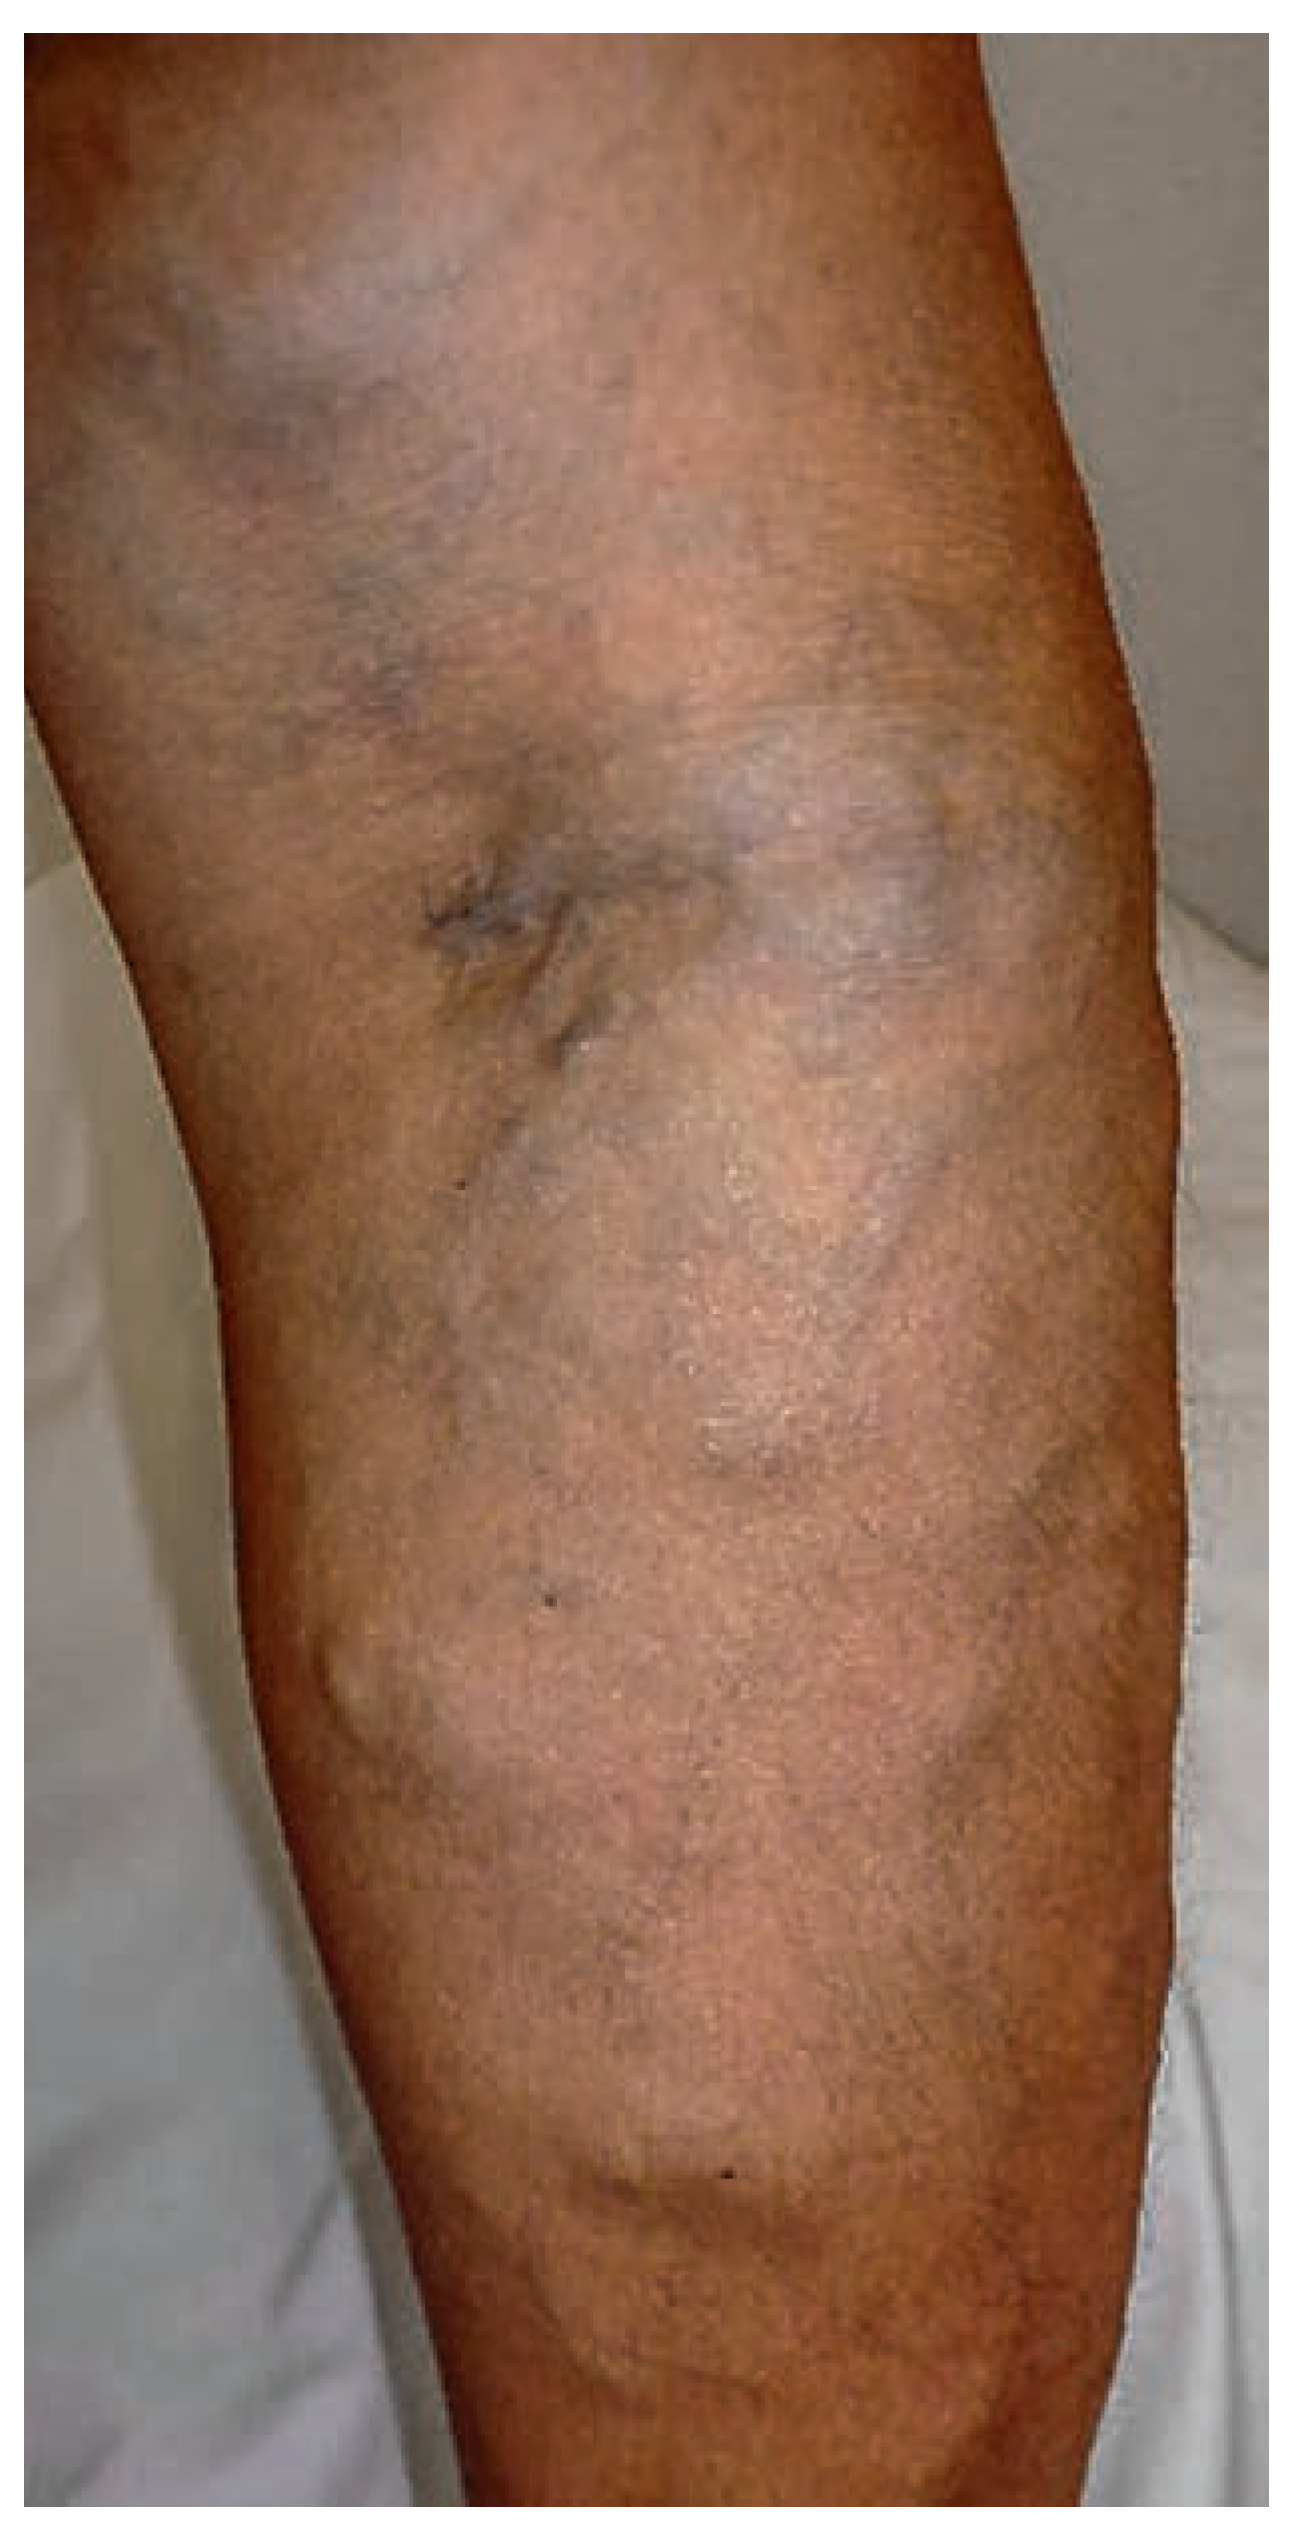

Venöse Malformationen

Kapillär-lymphatisch-venöse Malformation mit Überwuchs (Klippel-Trénaunay-Syndrom)